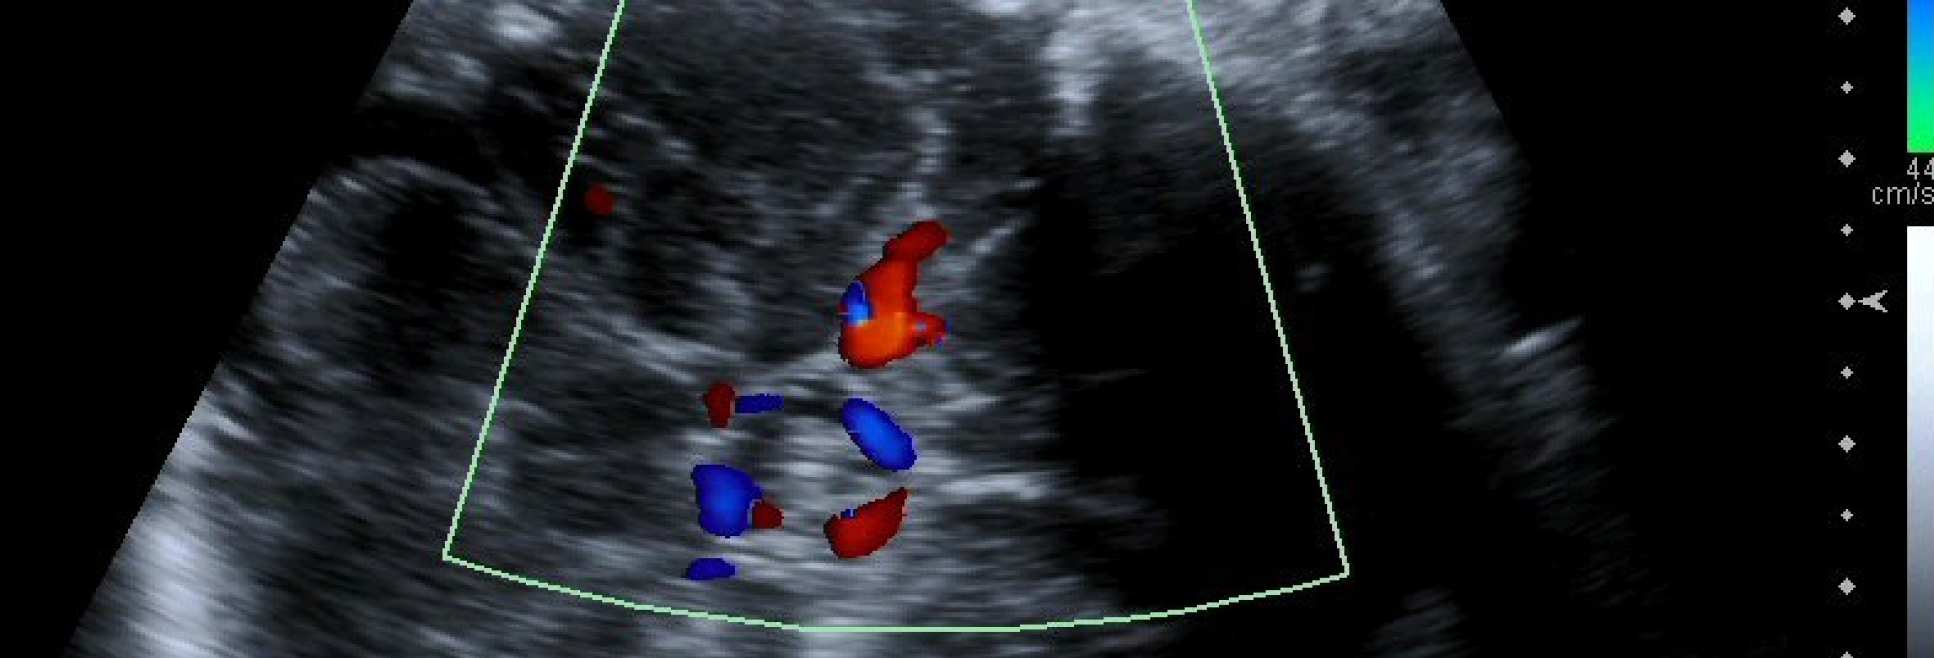

Our group was a founder member of the international TRUFFLE collaboration (Trial of Umbilical and Fetal Flow in Europe) leading to the multicentre TRUFFLE study which reported in 2015. This will be followed by the TRUFFLE 2 study in 2018, for moderately preterm babies, which will be run in 30+ European centres. We are expert in fetal assessment-particularly Doppler and computerised fetal heart rate tracing (cCTG); this is a pre requisite for such studies.

Our European collaboration in TRUFFLE since 2002 has enabled us to determine the optimum timing of delivery in severe preterm fetal growth restriction, which should be based on the ductus venosus (DV) Doppler together with fetal heart rate tracing. This work, published in the Lancet in 2015, has become highly cited and is becoming the basis of national and international guidelines. Follow on work has examined the role of cerebral Doppler in outcome, fetal heart rate monitoring and the effect of steroids in fetal growth restriction. The TRUFFLE group meets twice per year in different European venues.